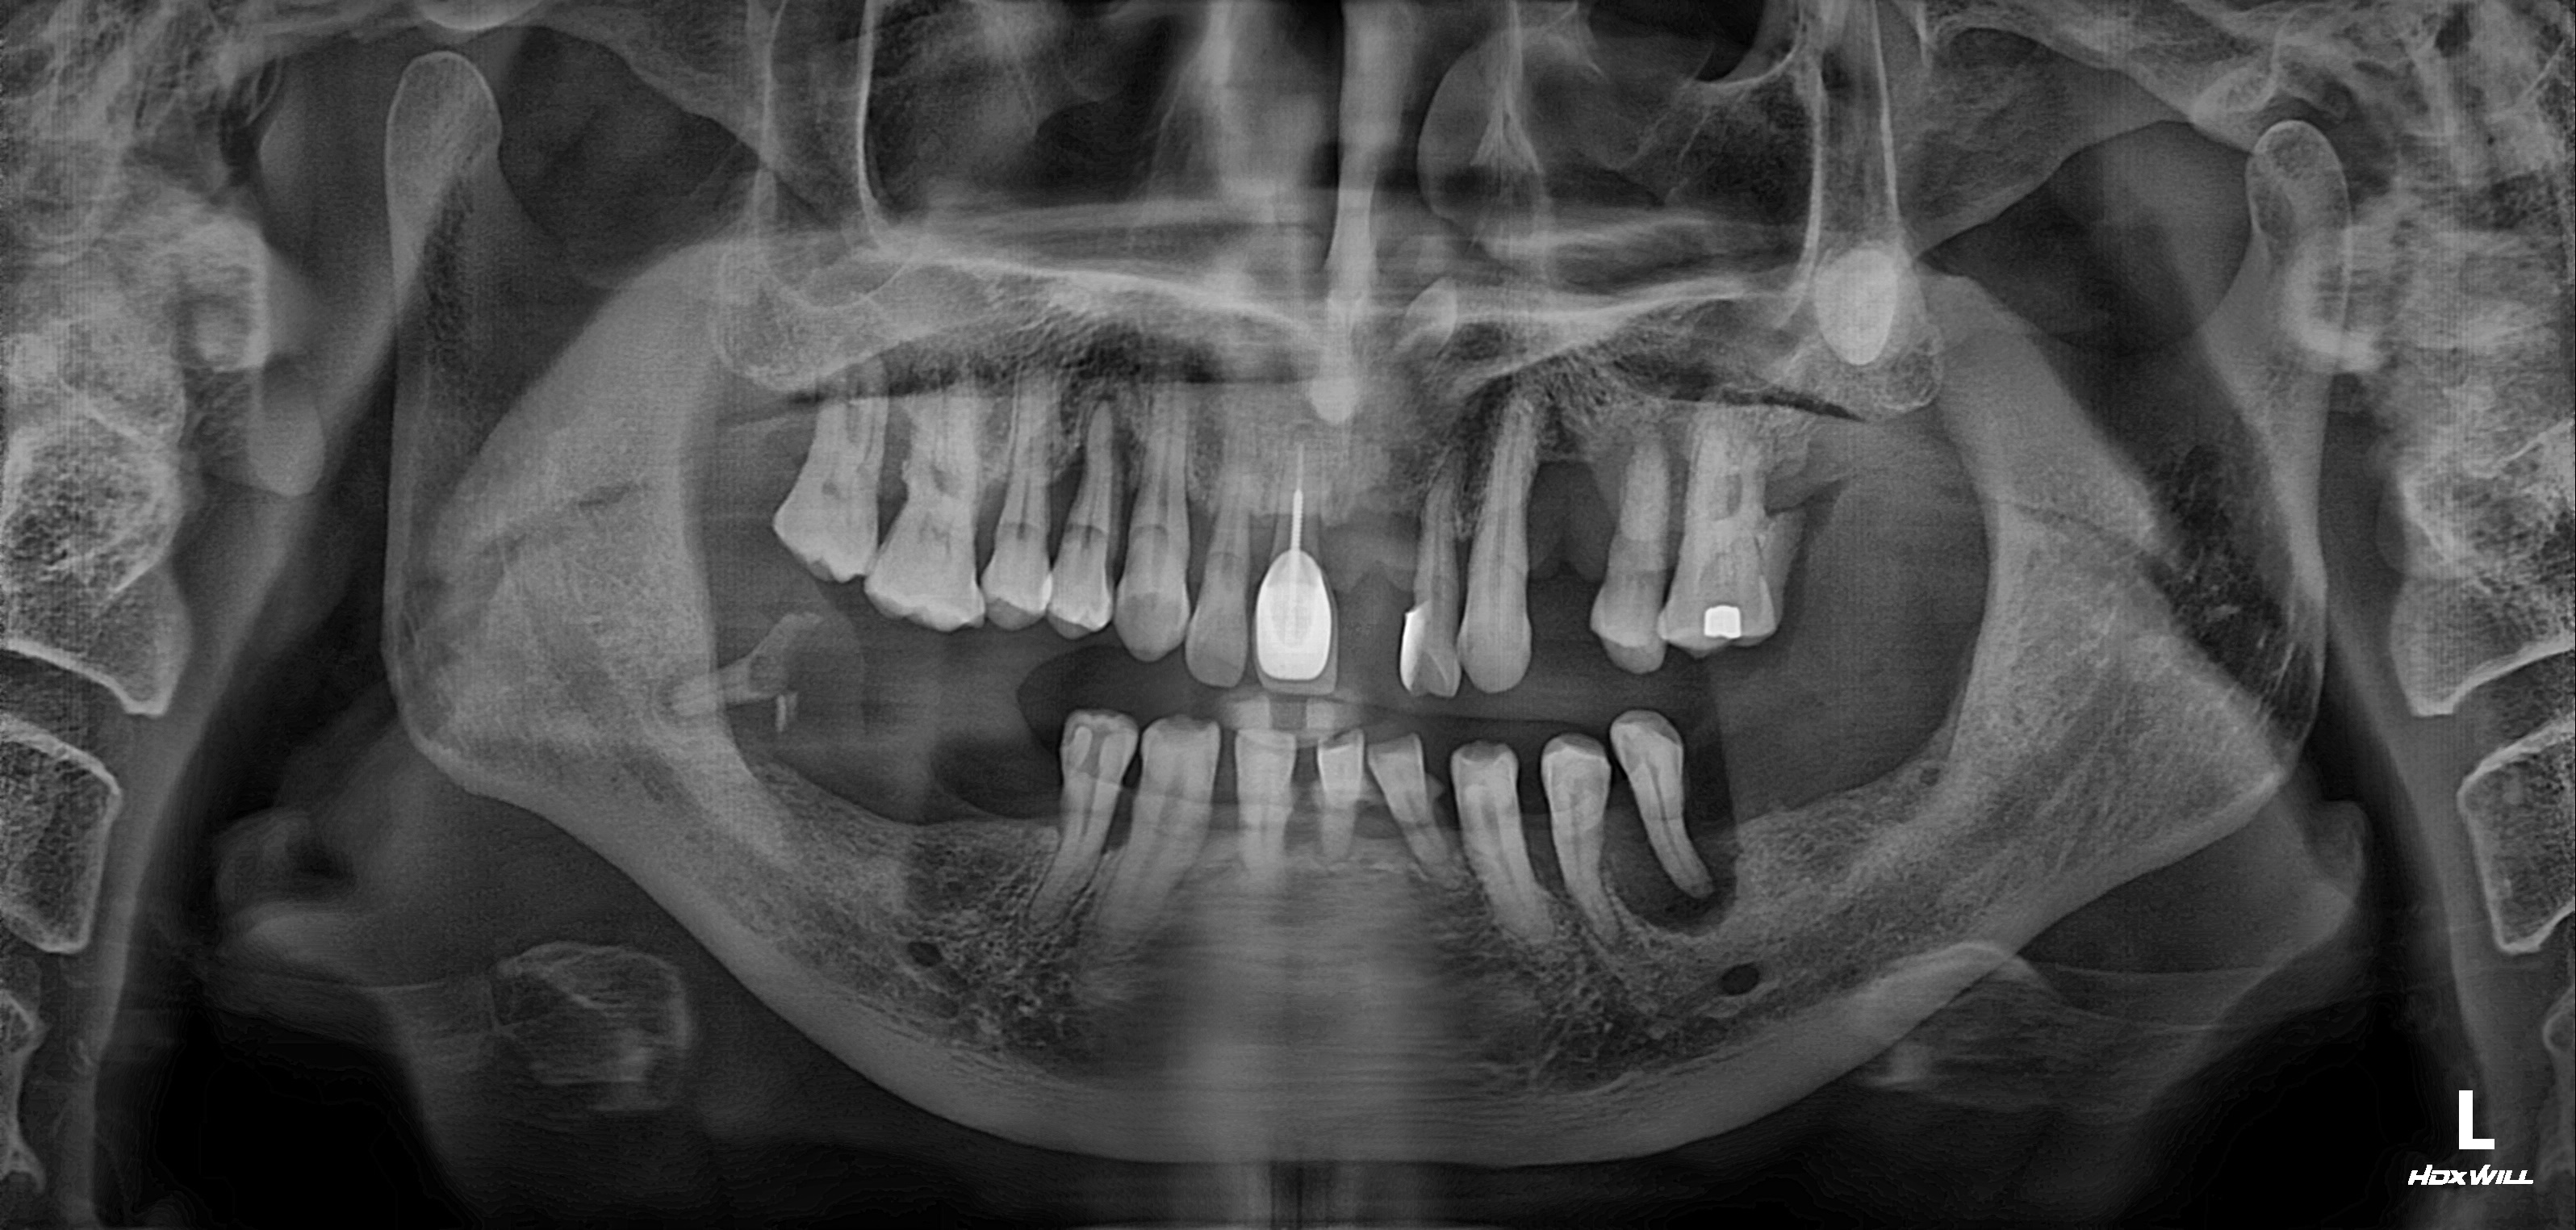

수술 전

수술 후

전악임플란트 식립사례

전후사진